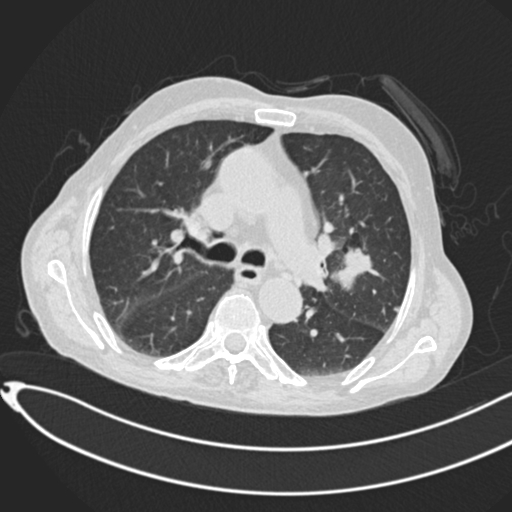

Analyzed Image

c.jpg

Uploaded: 2025-08-07 04:25:14Best Model Result

Malignant

Confidence: 74.4%

Model: EnhancedCNN

Ensemble Prediction

Confidence: 50.1%

Average of all modelsModel Predictions Comparison

ResNet50

Bengin:

28.0%

Malignant:

45.1%

Normal:

27.0%

ConfidenceDenseNet121

Bengin

49.0%

30.8%

20.2%

ConfidenceEnhancedCNN

10.4%

74.4%

15.2%